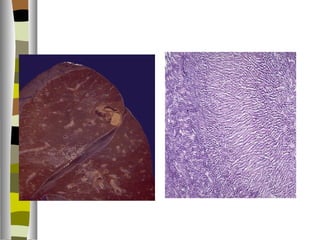

3. Virus Epstein –Barr ( mononucleosis infecciosa ) ( virus fam. Herpes )

enfermedad linfoproliferativa benigna.

fiebre / linfadenopatía generalizada / esplenomegalia / presencia de linf.T

activados y atípicos en sangre.